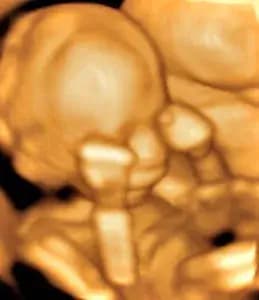

Week 9

Baby is about 1 inch long, and their fingers and toes are starting to form. They are developing their reproductive organs.